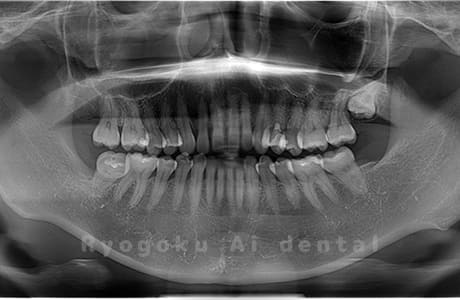

真っ直ぐ生えている親知らず

親知らずが真っ直ぐ生えているタイプです。

このタイプは真っ直ぐ生えていて咬み合わせに問題がなければ、抜歯しないケースもあります。ただし、虫歯になっていたり、痛みがあったり、咬み合わせが悪かったりすると抜歯をおすすめします。